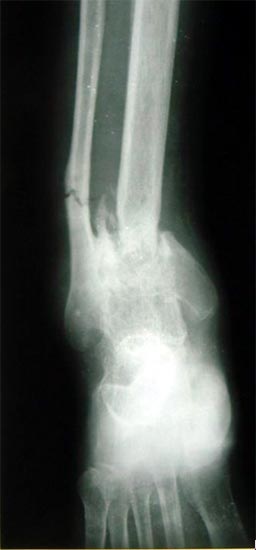

病例一、患者男性,23岁,胫骨开放粉碎骨折3年,外固定架固定,患处皮肤有贴骨瘢痕。扶双拐,患肢不能负重。

图1-1 X线片显示胫骨中上段粉碎骨折,有骨缺损、骨不连,

骨质吸收,骨折端变尖,断端硬化